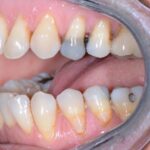

Nos réalisations : Conjointe

Céramique sur Zircone

La zircone présente une très grande résistance à la flexion (plus de 1 400 Mpa).

Translucide, elle reflète la lumière aussi naturellement que l’émail.

Biocompatible elle est garante d’une excellente intégration gingivale.